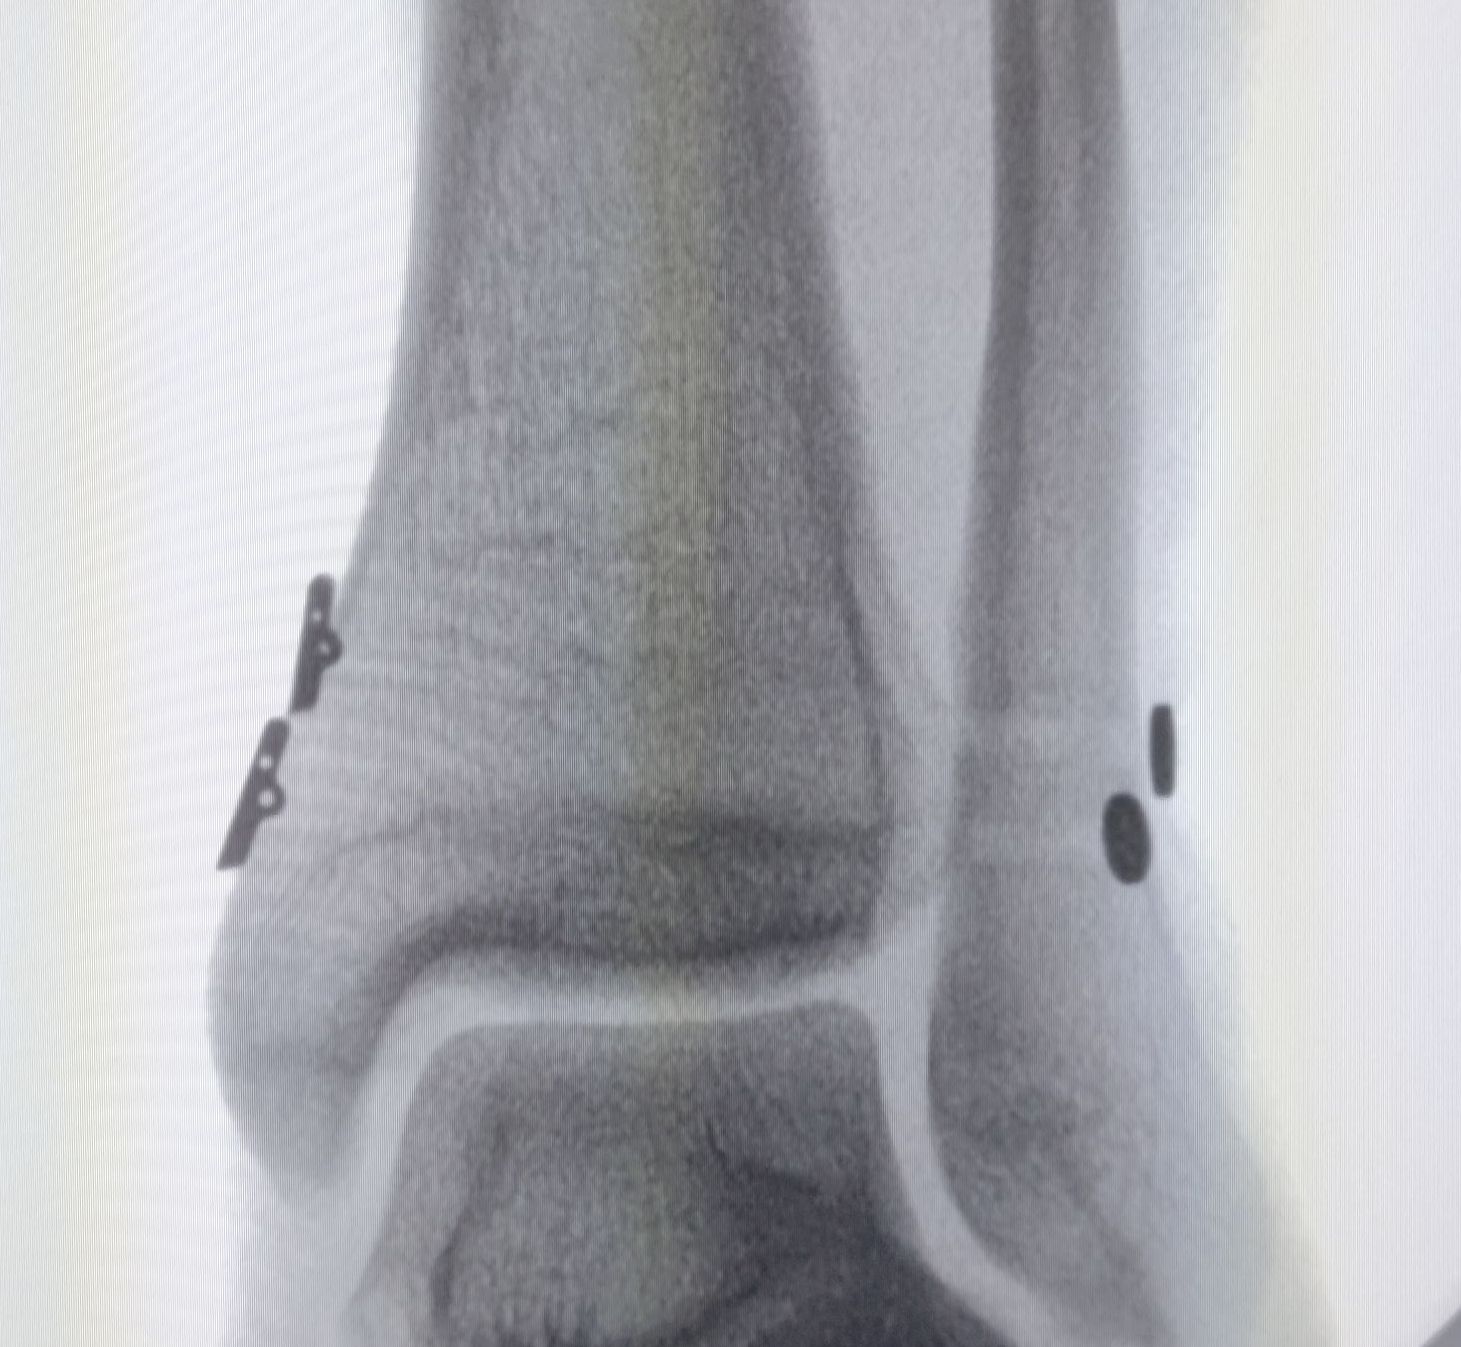

Cirurgia Artroscópica

Patologia do Tornozelo